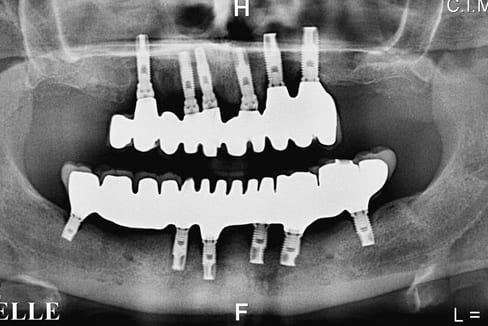

Z'etes pas sympa... surement parce que vous êtes jaloux d'avoir perdu un client comme moi au profit de dtxia !!! Je vous poste une photo et une radio des prothèses... seulement 14000 euros ça m'a couté !! En 3 rdv d'une heure en plus !! Je suis ravi !!

Pour Jeromami2 :je suis un peu inquiet de ton traitement

global sur implants;déjà des signes de résorption sur les2 implants distaux mandibulaires et un os peu vascularisé

mandibulaire et si tu fumes pour 33 euros sur 2 jours ;j'ai de sérieuses craintes pour l'avenir du traitement;tu

as déjà une fracture de la 11

tu as fait un coup "financier" mais si il y a des problèmes :dtexia

ne sera pas là pour les problèmes

c'est la différence avec les libéraux peut-être plus cher

mais ils sont toujours là et disponible pour reprendre

gratuitement quand ils sont à l'origine du traitement

bonne chance